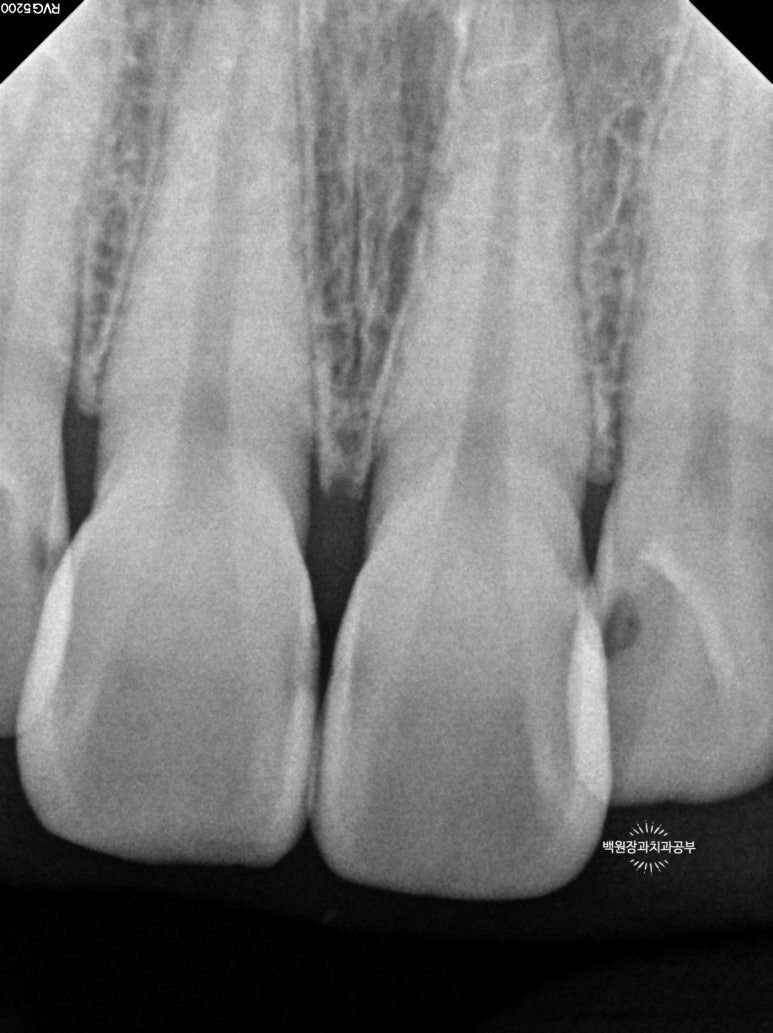

충치의 범위를 파악하기 위해 작은 엑스레이를 찍어봤어요.

Previous image Next image

총 세장의 치과용 치근단 방사선사진을 찍었고,

각 치아마다 옆면의 충치 범위를 확인할 수 있었어요!

까맣게 물들듯 보이는 곳들이 충기가 있는 곳입니다.

치과용 엑스레이 판독을 일반 사람이 하기는 힘드니깐,

제가 보기 쉽게 표시해 드릴께요!!

노란색으로 표시해 놓은 곳들이 옆면 충치가 있는 곳들이에요!

눈으로 확인하는 시진과 방사선 검사를 종합해서 합집합이 되는 부위를 모두 치료하면 됩니다.